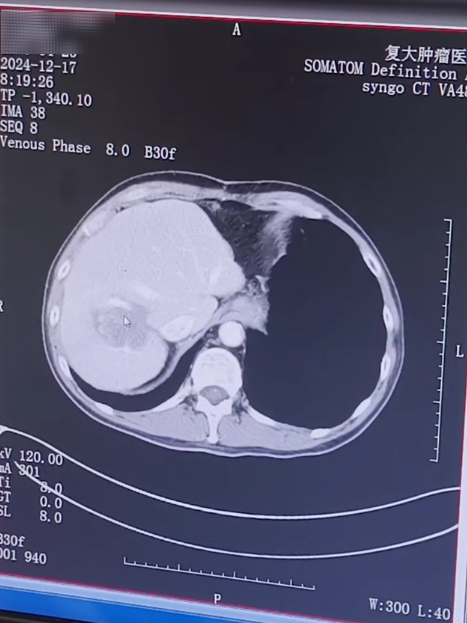

أشعر بحالٍ جيدة جدًا! لا أشعر بأي شيء تقريبًا، ولا يؤثر ذلك على أكلي أو شربي أو نومي. بعد أسبوع واحد من العلاج التدخلي، خضع العم وانج لعلاج التجميد لورم الكبد. بعد العملية، كان يتلقى علاجًا شاملاً بما في ذلك العلاج الموجه + العلاج المناعي + العلاج الكيميائي حسب الجدول الزمني. وفي أبريل/نيسان من هذا العام، أظهر الفحص المتابعة الذي أجراه العم وانغ أن الآفات النقيلية في الكبد قد تقلصت مقارنة بما كانت عليه من قبل، كما ضعف نشاطها بشكل كبير. ومع ذلك، كانت هناك العديد من الغدد الليمفاوية المتضخمة خلف الصفاق، والتي كانت أكبر وأكثر عددا من ذي قبل، لذلك عاد العم وانغ إلى جامعة فودان لتلقي العلاج مرة أخرى.

نتائج المراجعة في ديسمبر 2024

نتائج المراجعة في أبريل 2025